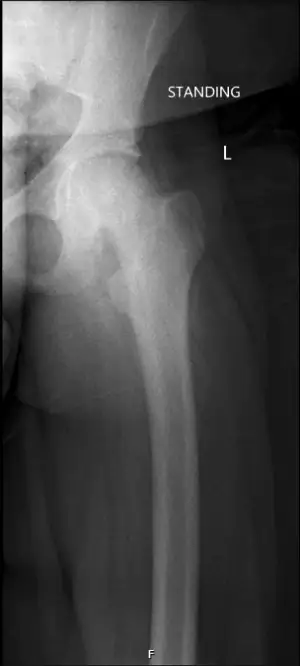

Upon return to the exam room to discuss the results of the tibia and fibula images, the patient’s gait was evaluated. An antalgic gait that favored the left lower extremity was observed, and his left leg and foot were held in external rotation. His antalgic gait in conjunction with the painful passive ROM of the left hip on initial exam led to the decision to obtain AP and lateral left hip radiographs (Figures 1A-1B). These images were reviewed with the on-call radiology resident, and it was suggested to image the bilateral hips for better comparison (Figure 1C). The final images of the bilateral hips were discussed with the on-call radiology resident, as well as the on-call orthopedic resident, to further delineate a possible diagnosis.

The patient’s history, physical exam, and radiographs were concerning for SCFE of the left hip. The urgent care radiographs had poor penetration and were not of the best quality to definitively make the diagnosis. Shared decision making with the urgent care physician, on-call orthopedic resident, and the patient’s mother, came to the conclusion that the patient should present to the pediatric emergency department (PED) at a local tertiary children’s hospital for further evaluation and better imaging.

The PED team repeated radiographs of the bilateral hips (Figure 2) with better penetration that confirmed the diagnosis of SCFE. The orthopedic service was consulted and recommended open reduction and internal fixation to repair the slip in an attempt to prevent avascular necrosis. He was admitted to the hospital under the orthopedic service, made non-weight-bearing status, and ordered nothing by mouth at midnight. He had labs drawn for thyroid stimulating hormone and vitamin D levels that were within normal limits. He was taken to the operating room the next morning and discharged home the same day following the procedure. After the surgery, he had 2 follow-up visits with orthopedics and was doing well.